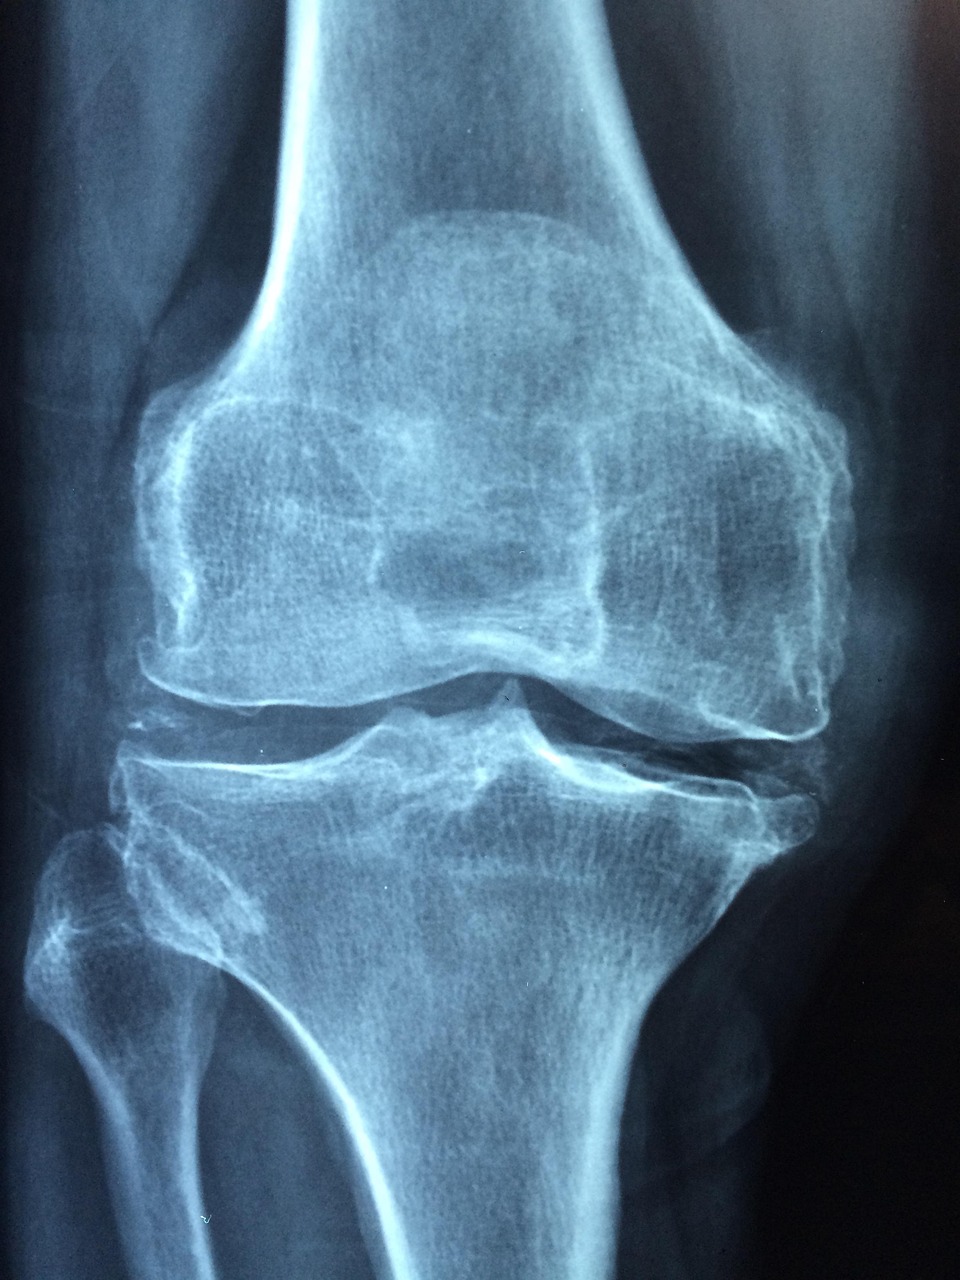

📷 사진 펼쳐보기 / 접기